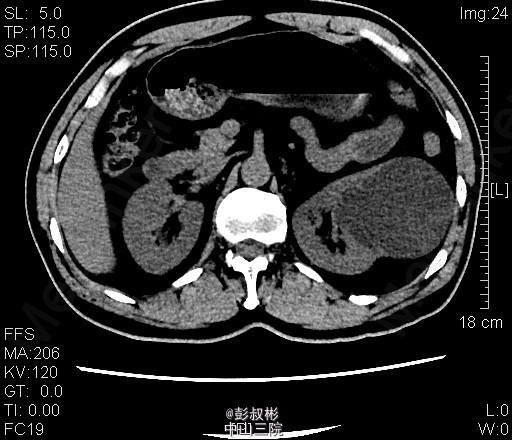

3、查体:腹稍膨隆,无压痛、反跳痛,未触及肿物,双肾区无红肿、隆起,无叩痛,双侧肋脊点、肋腰点无压痛。腹平软,双侧上中输尿管点无压痛,膀胱区无压痛。双侧腹股沟区未触及肿物。 4、CT:双肾多发囊肿,左肾囊肿较大,推压左侧肾盂肾盏。左肾小结石.轻度弥漫性脂肪肝

5、左肾囊肿 6、住院后完善相关检查,查血、尿常规,生化,凝血,心电图,胸片等未见明显异常。CT:双肾多发囊肿,左肾囊肿较大,推压左侧肾盂肾盏。左肾小结石.轻度弥漫性脂肪肝。经术前准备,行单孔腹腔镜下肾囊肿去顶术,手术顺利,术后予预防感染、营养支持等治疗,术后恢复较好,术后病理示:左肾囊肿。